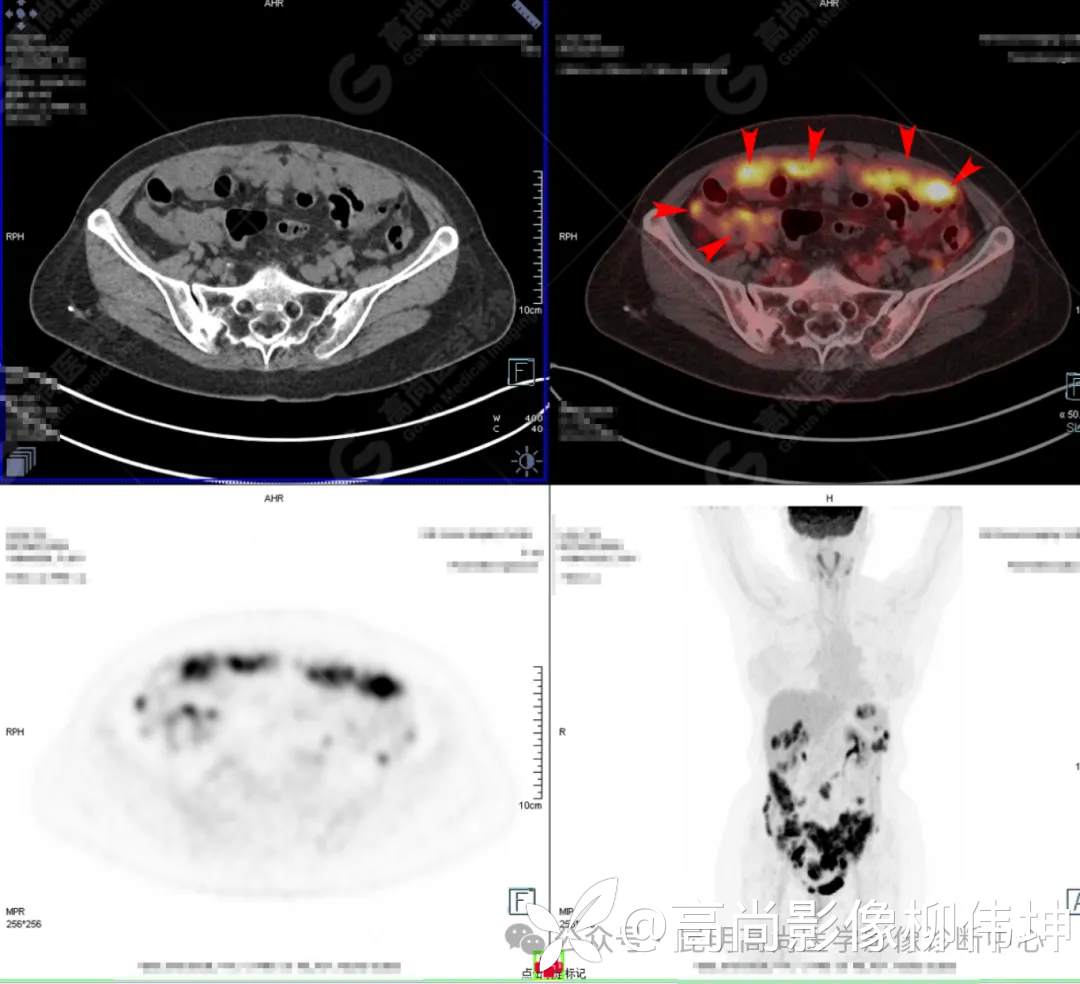

囊腺癌PET/CT检查在腹膜和淋巴以及全身转移灶的显示上很有优势,如下图为另一患者PET/CT图像:

(3)PET-CT表现:典型者FDG PET/CT表现为附件区异常放射性浓聚灶;淋巴结转移、腹内种植转移常出现FDG的异常浓聚。